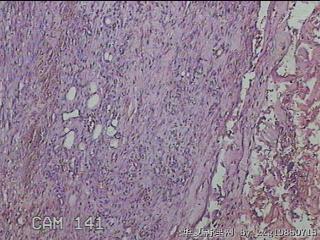

左肘部包块

性别

男

年龄

39

临床诊断

左肘部肿物:炎性脂肪瘤

一般病史

发现左肘部肿物1周。

标本名称

大体所见

灰白粉红色组织2x1.8x0.3㎝一团,表面结节状,光滑,切面灰白粉红色,质软。

图2

纤维组织细胞瘤

有外伤史吗,考虑结节性筋膜炎。

首先考虑结节性筋膜炎。

梭形细胞肿瘤,待免疫组化